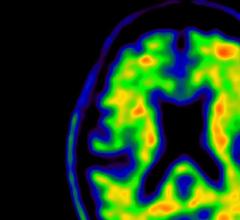

Neuro Imaging

Neuro imaging produces images of the structure or activity of the nervous system, usually the brain. It uses techniques like magnetic resonance imaging (MRI) and computerized tomography (CT).